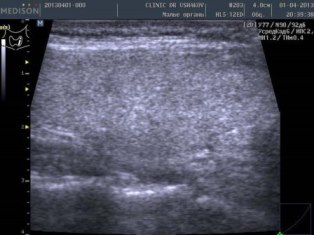

После лечения (апрель 2013; после 4-х курсов и полной отмены тиреостатического средства) |

В левой доле ткань значительно улучшилась: 1) при участии иммунной системы утилизировались участки разрушенной ткани, имеются лишь единичные мелкие (точечные) места истощения, 2) почти полностью исчезла лимфоидная инфильтрация (заметны лишь остаточные мало выраженные участки) |